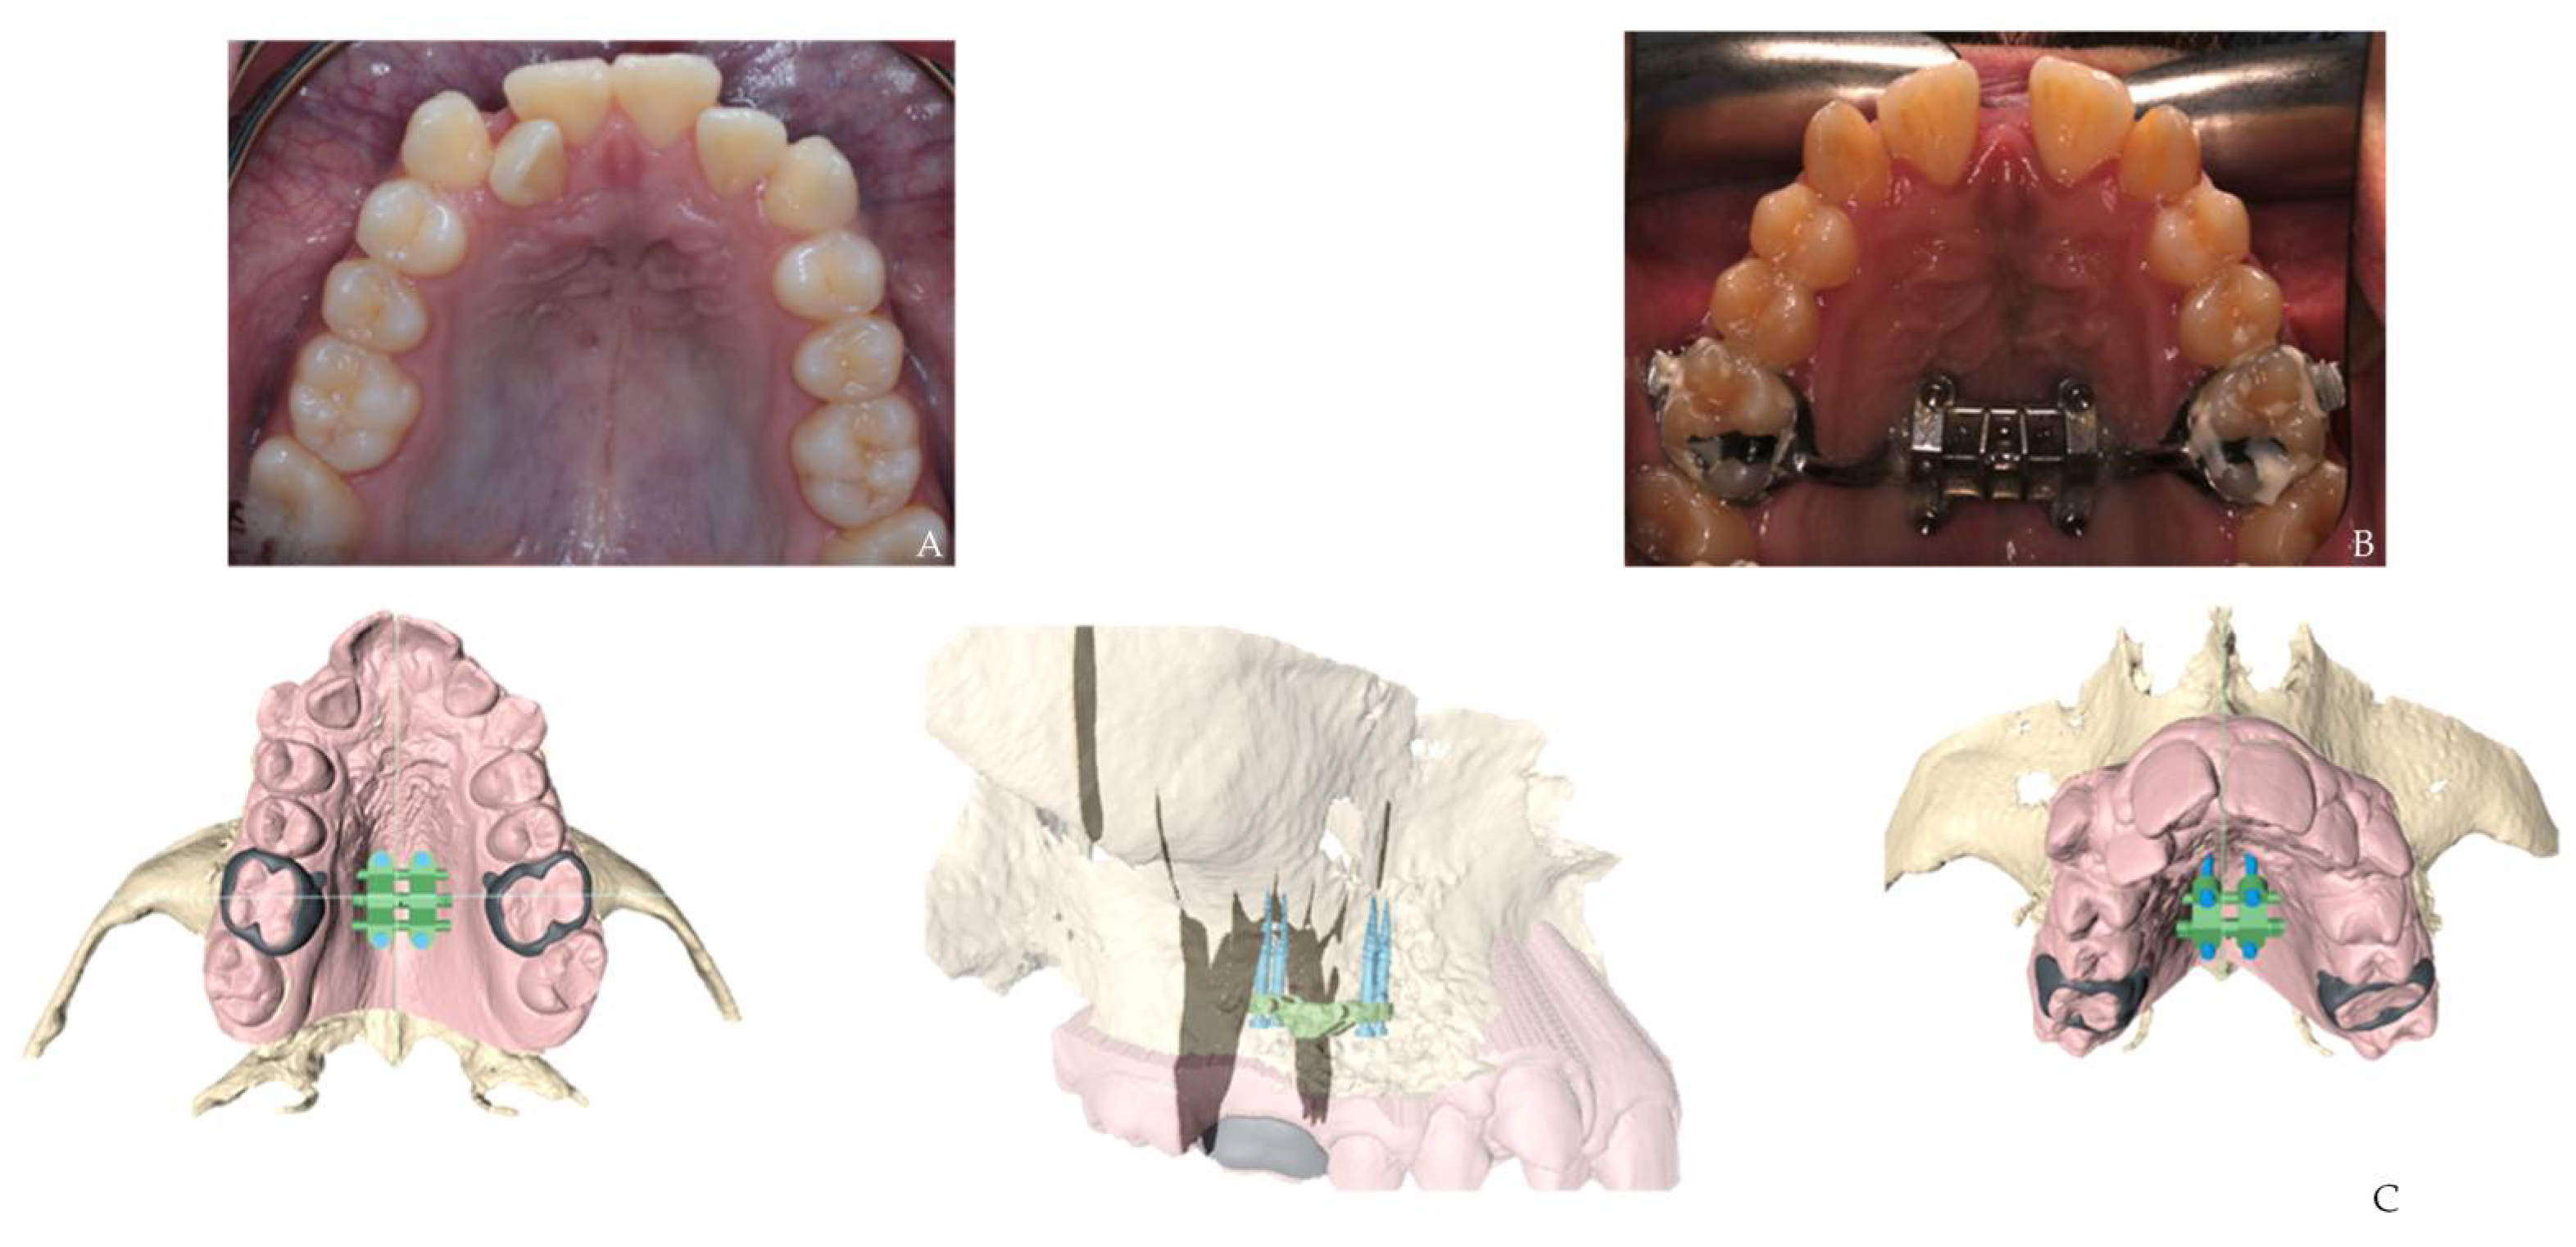

3.4. Corticotomy Technique Using CAD/CAM 3D Printed Surgical Guides